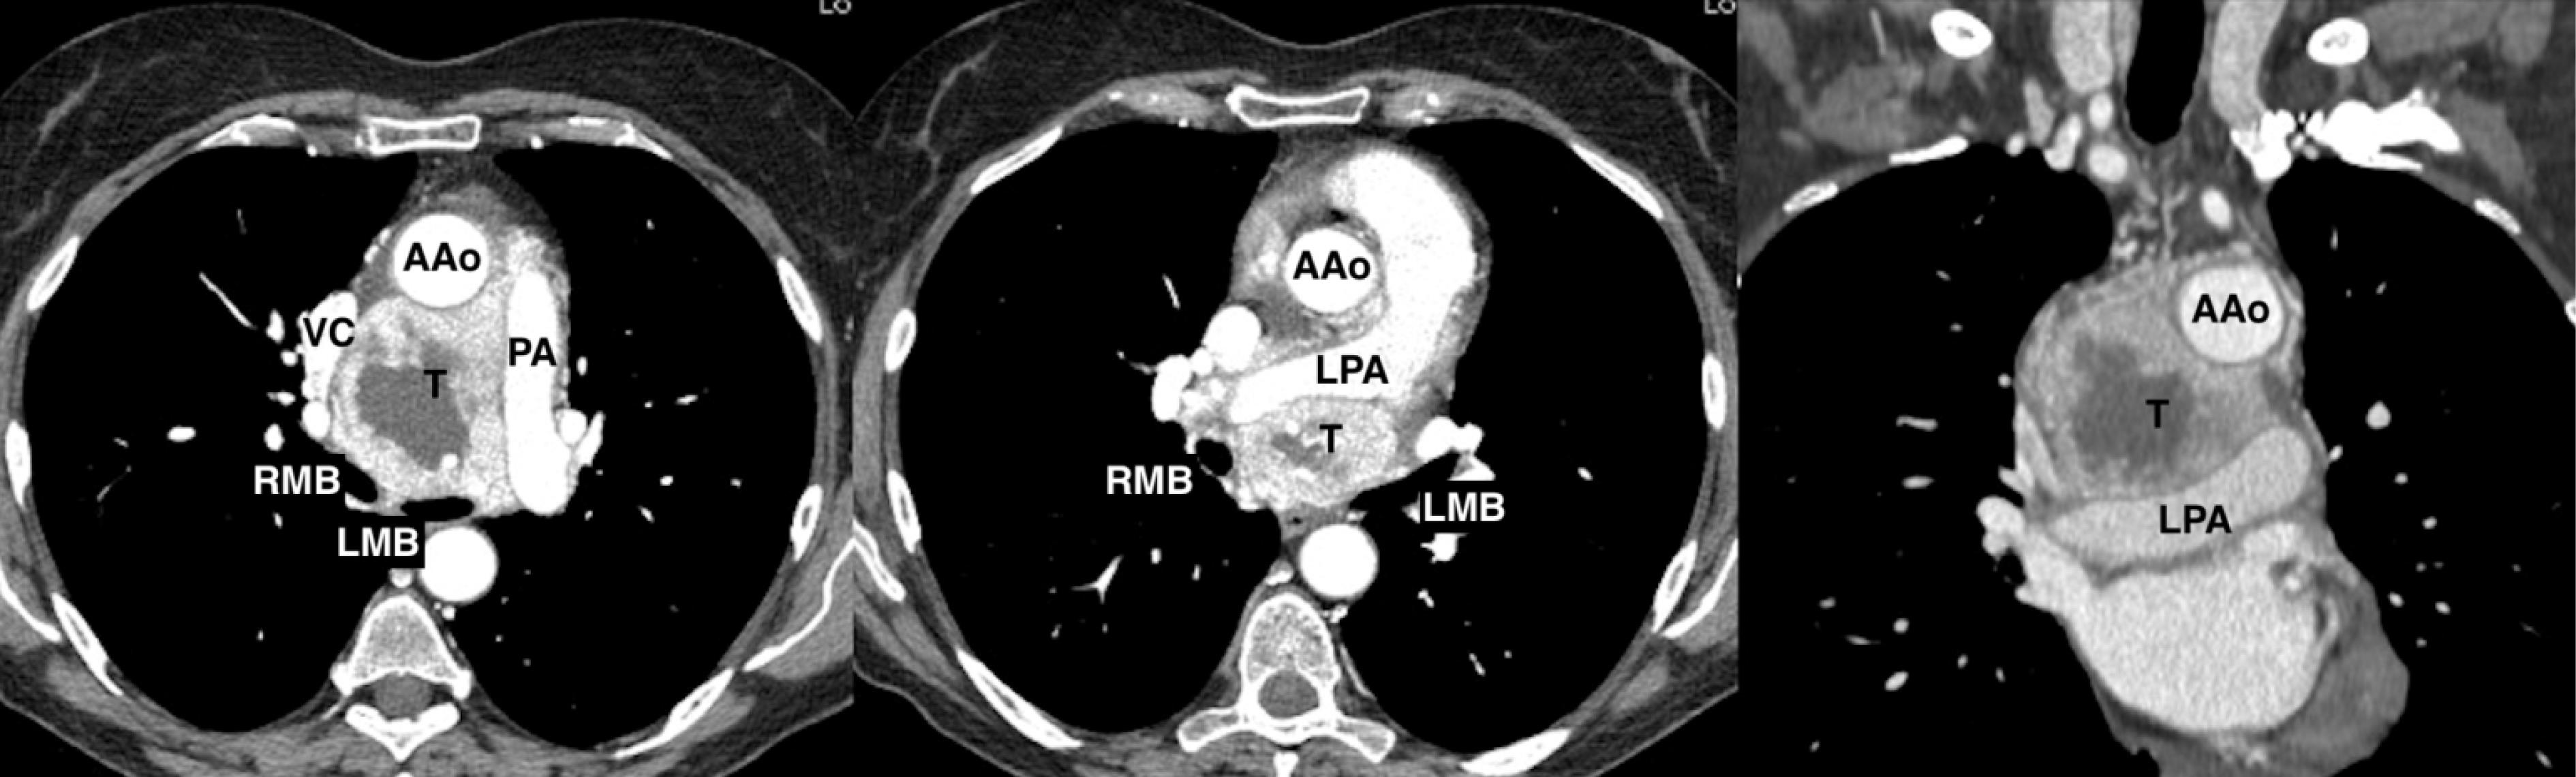

We report a case of a 67-year-old female who was incidentally diagnosed with a middle indeterminate mediastinal mass. Her past clinical history was characterized byarthritic symptoms as joint pain, loss of motion and inflammation. During follow-up, a Positron Emission Tomography (PET-scan) revealed a 9-cm middle mediastinal mass with a peripheral standardized uptake value (SUV = 20) with no evidence of extrathoracic uptake (Figure 1). A chest CT-scan revealed a large 70x60x30 mm well enhanced mass with necrotic central areas, located between the superior vena cava and the posterior portion of the ascending aorta, compressing the left atrium and, the trachea and main left bronchus posteriorly, surrounding the right pulmonary artery (Figure 2). A right uniportal video-thoracoscopic (U-VATS) biopsy of lesion was performed with a severe but controlled intraoperative bleeding. However, the mass remained undiagnosed so that a followed endobronchial-ultrasound transbronchial needle-aspiration (EBUS-TBNA), was suggestive of a paraganglioma. The patient was referred to surgery after multidisciplinary tumor board. A pre-operative coronarography revealed that the mass was perfused by a large tortuous vessel originating from the circumflex artery and smaller ones from the right coronary artery (Figure 3).

Figure 2.

Axial and coronal enhanced chest computed scan (CTscan) showing a solid, highly peripherally vascularized, 7x6x3 cm mass in the middle mediastinum with low-density contrast enhancement in the central area; the tumor (T) was adjacent to the ascending aorta (AAo), superior vena cava (VC), atrium, surrounded the left pulmonary artery (LPA) and was tenaciously sticking to the trachea and the main bronchi (LMB, RMB). PA: Pulmonary artery